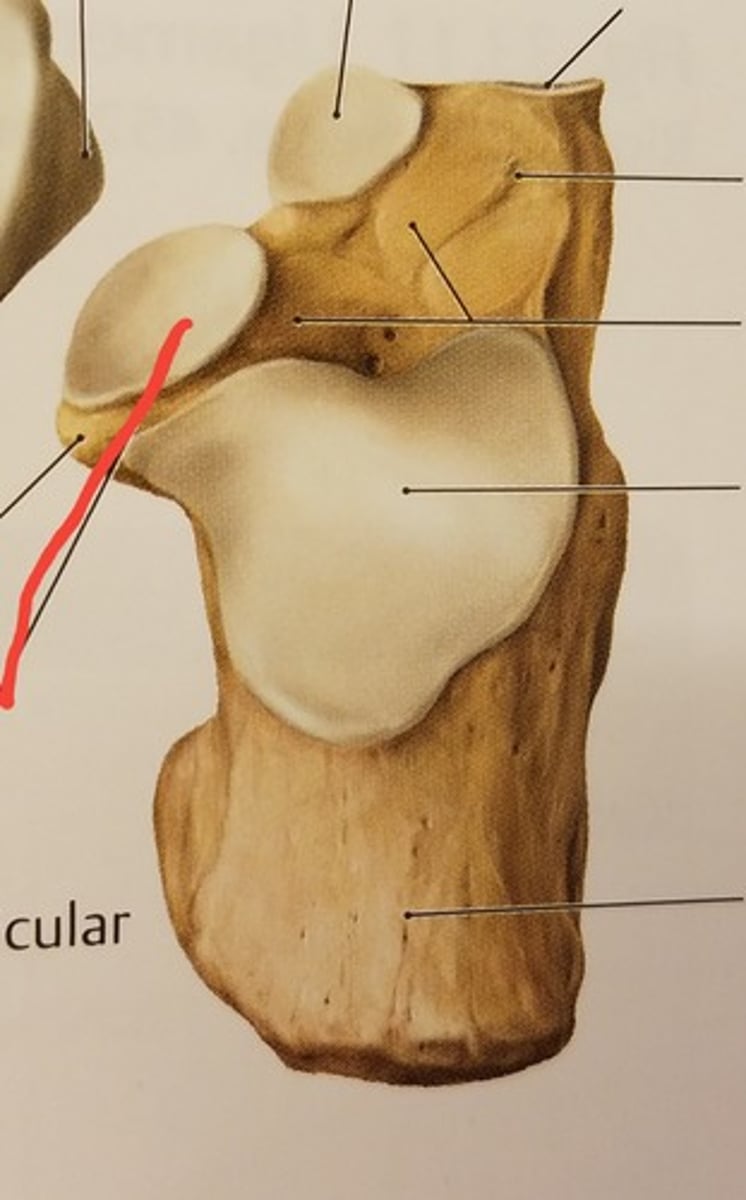

Patella

Apex

inferior surface for patellar ligament

Base

superior surface for quadriceps tendon

Medial articular surface (for medial condyle of femur; smaller)

green

Lateral articular surface (for lateral condyle of femur; bigger)

green